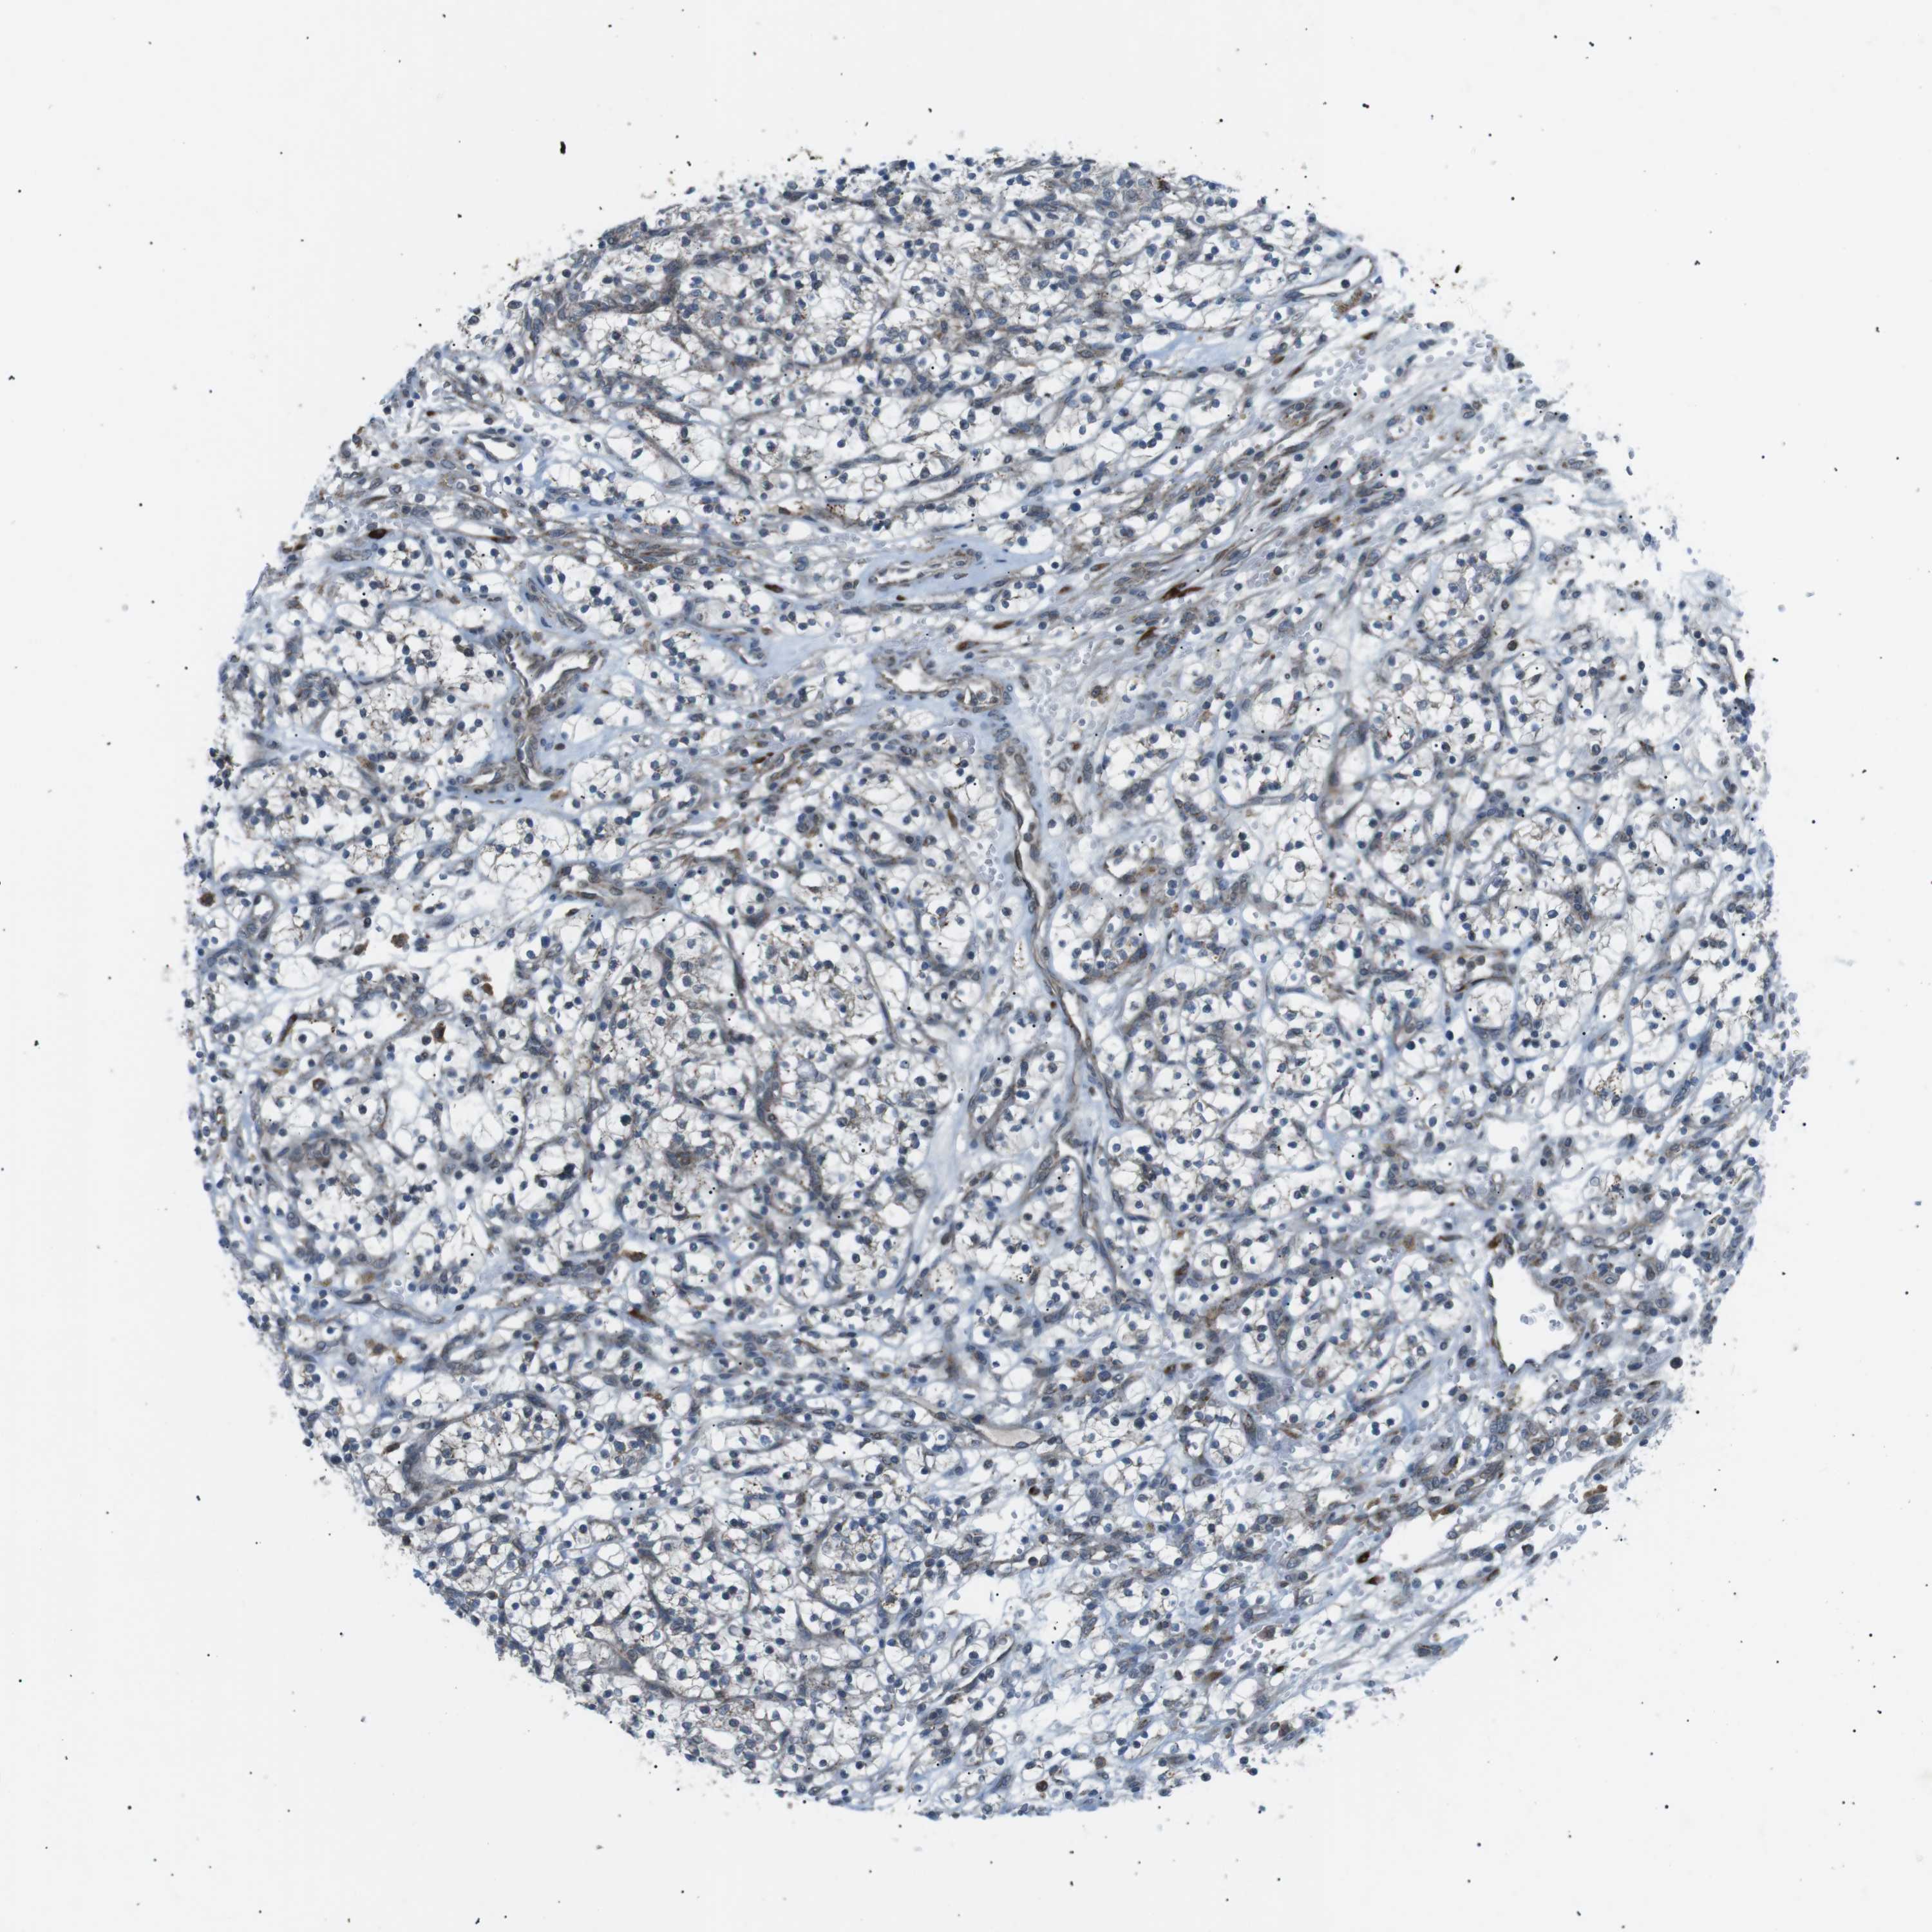

KIDNEY RENAL CLEAR CELL CARCINOMA (VALIDATION) - Interactive survival scatter ploti

The Survival Scatter plot shows the clinical status (i.e. dead or alive) for all individuals in the patient cohort, based on the same data that underlies the corresponding Kaplan-Meier plots. Patients that are alive at last time for follow-up are shown in blue and patients who have died during the study are shown in red.

The x-axis shows the expression levels (FPKM) of the investigated gene in the tumor tissue at the time of diagnosis. The y-axis shows the follow-up time after diagnosis (years). Both axes are complimented with kernel density curves demonstrating the data density over the axes. The top density plot shows the expression levels (FPKM) distribution among dead (red) and alive patients (blue). The right density plot shows the data density of the survived years of dead patients with high and low expression levels respectively, stratified using the cutoff indicated by the vertical dashed line through the Survival Scatter plot. This cutoff is automatically defined based on the FPKM cutoff that minimizes the p-score. The cutoff can be changed by dragging the vertical line or by entering a cutoff value in the square labeled "Current cut-off".

Under the Survival Scatter plot the p-score landscape (black curve; left axis) is shown together with dead median separation (red curve; right axis). Dead median separation is the difference in median mRNA expression between patients who have died with high and low expression, respectively. It is calculated as follows: median FPKM expression of dead patients with high expression - median FPKM expression of dead patients with low expression. This is intended to aid the user in visually exploring custom cutoffs and the associated p-scores and dead median separation.

Individual patient data is displayed and can be filtered by clicking on one or more of the category buttons on the top of the page. Categories describing expression level and patient information include: high, low, alive, dead, female, male and tumor stages. The scale of the x-axis can be toggled between linear and log-scale by clicking on the "x log" button. Mouse-over function shows TCGA ID, patient information and mRNA expression (FPKM) for each patient.

& Survival analysisi

Kaplan-Meier plots summarize results from analysis of correlation between mRNA expression level and patient survival. Patients were divided based on level of expression into one of the two groups "low" (under cut off) or "high" (over cut off). X-axis shows time for survival (years) and y-axis shows the probability of survival, where 1.0 corresponds to 100 percent.

ARID5B is validated prognostic, high expression is favorable in Kidney Renal Clear Cell Carcinoma (validation)

Best expression cut offi

: 26.64

Average pTPM 24.4

Number of samples 100